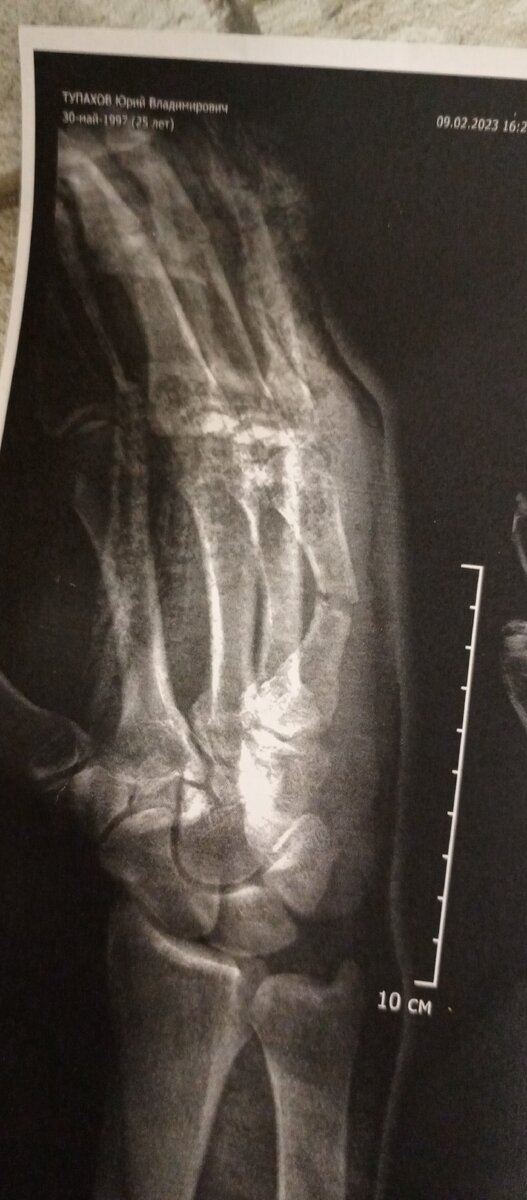

Здравствуйте дорогие читатели, сегодня я начинаю свой канал и начинаю с того что со мной произошло вчера. А случилось следующее, это был обычный рабочий день, проснулся умылся улыбнулся, выхожу из подъезда и происходит это, я подскальзываюсь падаю на правую руку. Было больно но не сильно, пришла мысль что я выбил палец и что все будет хорошо, сходил на работу все хорошо но рука болит когда происходит сильное напряжение. Понимаю что то не так я собираюсь и еду в больницу, думаю может ушиб сейчас скажут купить мазь и все будет хорошо, но нет оказалось перелом, перелом кости за мизинцем, но казалось бы, что там страшного гипс положат и все будет нормально но нет. Все подходит к тому что нужно ставить пластину чтобы кость срослась ровно. Вот теперь в раздумьях что делать, оставить все как есть или поставить пластину для ровного сростания